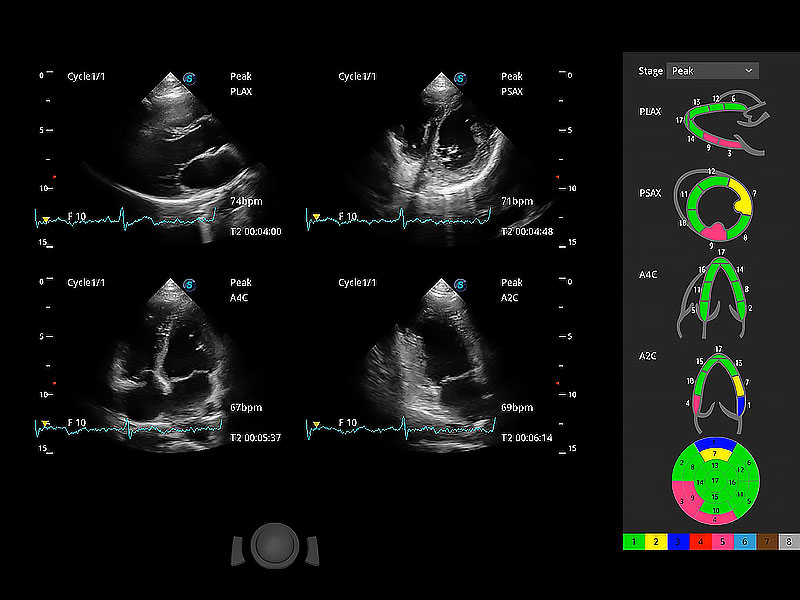

通過心肌識別技術(shù)與二維斑點(diǎn)追蹤技術(shù)相結(jié)合,對心臟的超聲圖像進(jìn)行量化分析。計算心肌17個節(jié)段的應(yīng)變、應(yīng)變率、速度、位移等,并通過牛眼圖的形式進(jìn)行呈現(xiàn)。

具備多種協(xié)議可選,同時支持17階段劃分法和專業(yè)的SE報告。